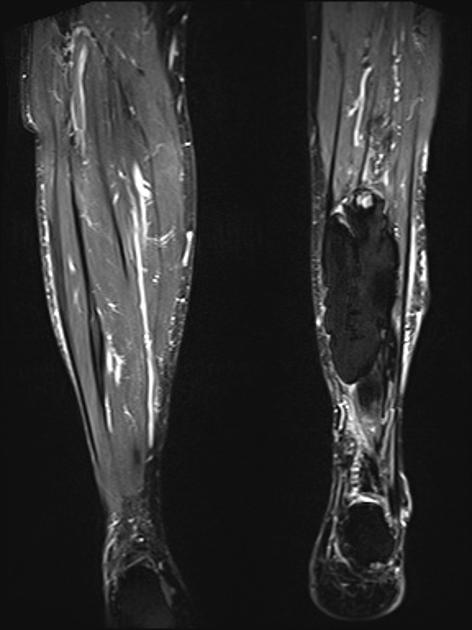

MRI may be used as a means of assessing the extent of the lesion. In the early phase, the lesion is isointense to muscle on the T-1 weighted images and hyperintense to muscle on T-2. As progressive ossification of the periphery occurs in the subacute phase, there will be the formation of a hypointense outer rim on the T-1 weighted images (3). Enhancement is present on the post-contrast images. With further maturation, the lesion becomes hypointense on both the T-1 and T-2 weighted sequences.

Figure 5 is a T-1 weighted image of an MO lesion in the left lower leg. It is fairly isointense to muscle on this image with a low signal periphery. Figure 6 is an accompanying STIR image, which demonstrates a fatty component and thus manifests a uniformly low signal.